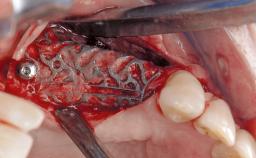

Ridge Preservation and Implant Placement for a Fixed Dental Prosthesis After a Car Accident

It is well known to clinicians that any removal of teeth will, over time, cause the dimensions of the alveolar ridge to be reduced by resorption of the bundle bone and by changes related to external modeling. This development is particularly evident in the crestal region with its thin buccal bone that consists of bundle bone almost entirely. The facial bone will rapidly resorb as blood supply from the periodontal ligament gets disrupted (Araújo and Lindhe 2005). There is no reason why traumatic tooth loss should not have the same consequences. It takes more than achieving implant osseointegration for a treatment outcome to be considered successful. No deficiency of bone or soft tissue is acceptable when an ideal esthetic outcome is the goal. Several articles (Sanz and coworkers 2011; Vignoletti and coworkers 2011) have reported on techniques of improving the alveolar ridge for implant treatment, notably focusing on protecting tissues from resorption.

Bone Augmentation Horizontal|Simultaneous|Sinus Floor Elevation|Staged